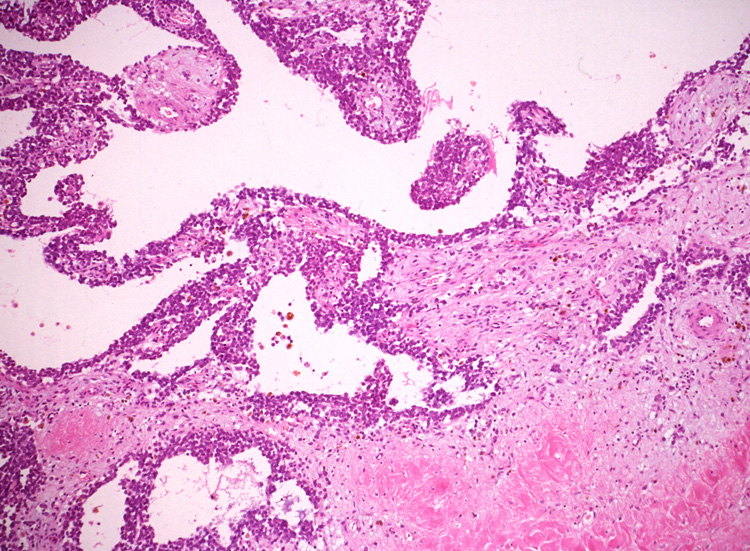

ルーペ像では(Fig.01)ヘモジデリンを貪食したマクロファージに富む線維性間質をもち、腫瘍細胞が胞巣状, 地図状に増殖している。線維性間質はdesmoplasticではなく成熟した線維組織のようである。本例ではさらに腫瘍胞巣内にタンパク液の貯留した偽嚢胞様構造が散在するほか、層状の腫瘍細胞に裏装された嚢胞様構造が出現している。(Fig.03,04)

腫瘍細胞はシート状密に増殖する、類円形小型淡明な核をもった細胞質の乏しい細胞からなる。細胞分裂像は目立たなかった。(Fig.05,06), 線維間質部分の拡大所見。腫瘍細胞が小さな集簇をつくって浸潤している。(Fig.07) Fig08では血管周囲性ロゼットが認められる。